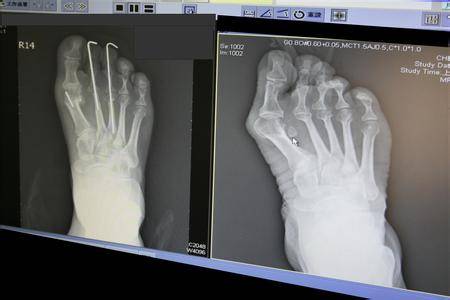

在2011年时,贝嫂就因非常严重的大脚趾外翻,

被专业医生要求放弃高跟鞋,但是她没有听。

大脚趾外翻非常严重。

大脚趾外翻不仅影响美观,而且会持续疼痛,严重的时候无法走路,如果去做手术矫正,即使手术成功,也留下了难看的疤痕,在那之后只能穿厚底鞋。